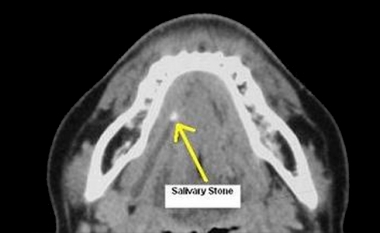

Een ander vaak voorkomend probleem is zwelling t.g.v. stuwing in de klier door steenvorming. Dit zien we vaak bij de speekselklier die ter hoogte van de kaakhoek ligt. Een kenmerk is, dat de klier snel opzwelt tijdens de maaltijd en soms zo groot wordt al een ei. Na de maaltijd neemt de zwelling weer geleidelijk af.

Bij de diagnostiek wordt bekeken waar de steen ligt. De steen kan liggen in de afvoerbuis welke in de mondbodem loopt of in de klier. Als de steen op een gunstige plek ligt in de afvoerbuis kan meestal volstaan worden met het verwijderen van de steen. In de meeste gevallen kan dit onder plaatselijke verdoving. Als de steen in de klier ligt, moet meestal de speekselklier verwijderd worden. Dit gebeurt onder narcose via een snede in de hals ter hoogte van de kaakhoek.